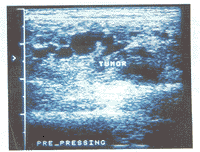

图4 前臂皮下软组织内血管畸形,内为迂曲扩张的管道与软组织结构相间的回声,边界模糊

所有血管畸形在高频灰阶超声图像上亦表现为一团块状结构。但17处(85.0%)病变内为迂曲扩张的管道或管道与软组织相间的回声(图4),仅3处(15.0%)表现为单纯的实质性团块,10处(50.0%)伴有钙化。多普勒超声显示病变内血流信号稀少,血管密度为0~4条/cm2[(2.3±1.0)条/cm2],PSV仅为4.7~78.0 cm/s[(27.4±15.0)cm/s],RI为0.5~1.0(0.7±0.1)(图5,6)。